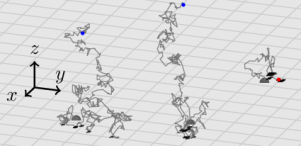

The spots in the considered images are the result of particles generated by cells (reaction) during a time window . These cells (hereon, active cells) are immobilized at the bottom of a well, i.e. on the plane . The particles they generate undergo a Brownian motion through a medium (diffusion), modeled here by the half-space . When these particles collide with the plane , they can bind to an even coat of receptors that covers it (adsorption), and after some time, they can break the bond and continue their motion (desorption). At time , the experiment finishes and the density of bound particles is imaged. Fig. 1 exemplifies this physical model at a particle level and exhibits a section of a real image from a Fluorospot immunoassay.

|

|

| (a) Particles’ motion model | (b) Typical observation |